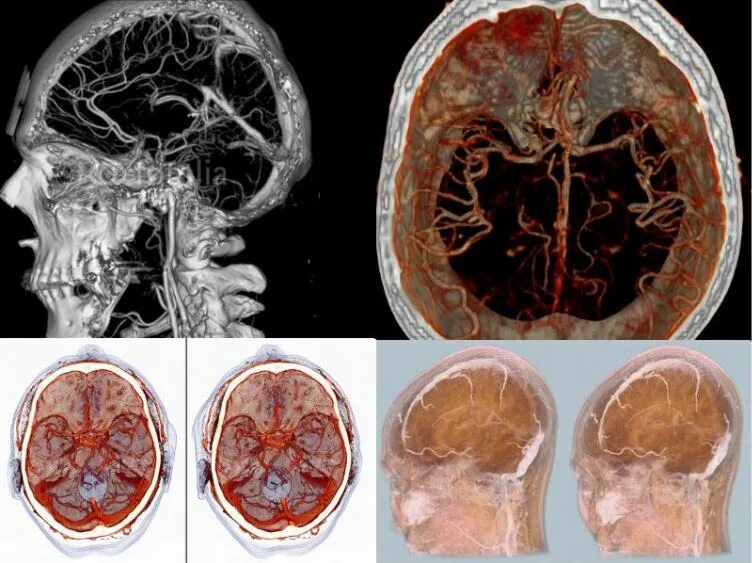

Мрт с контрастированием головного